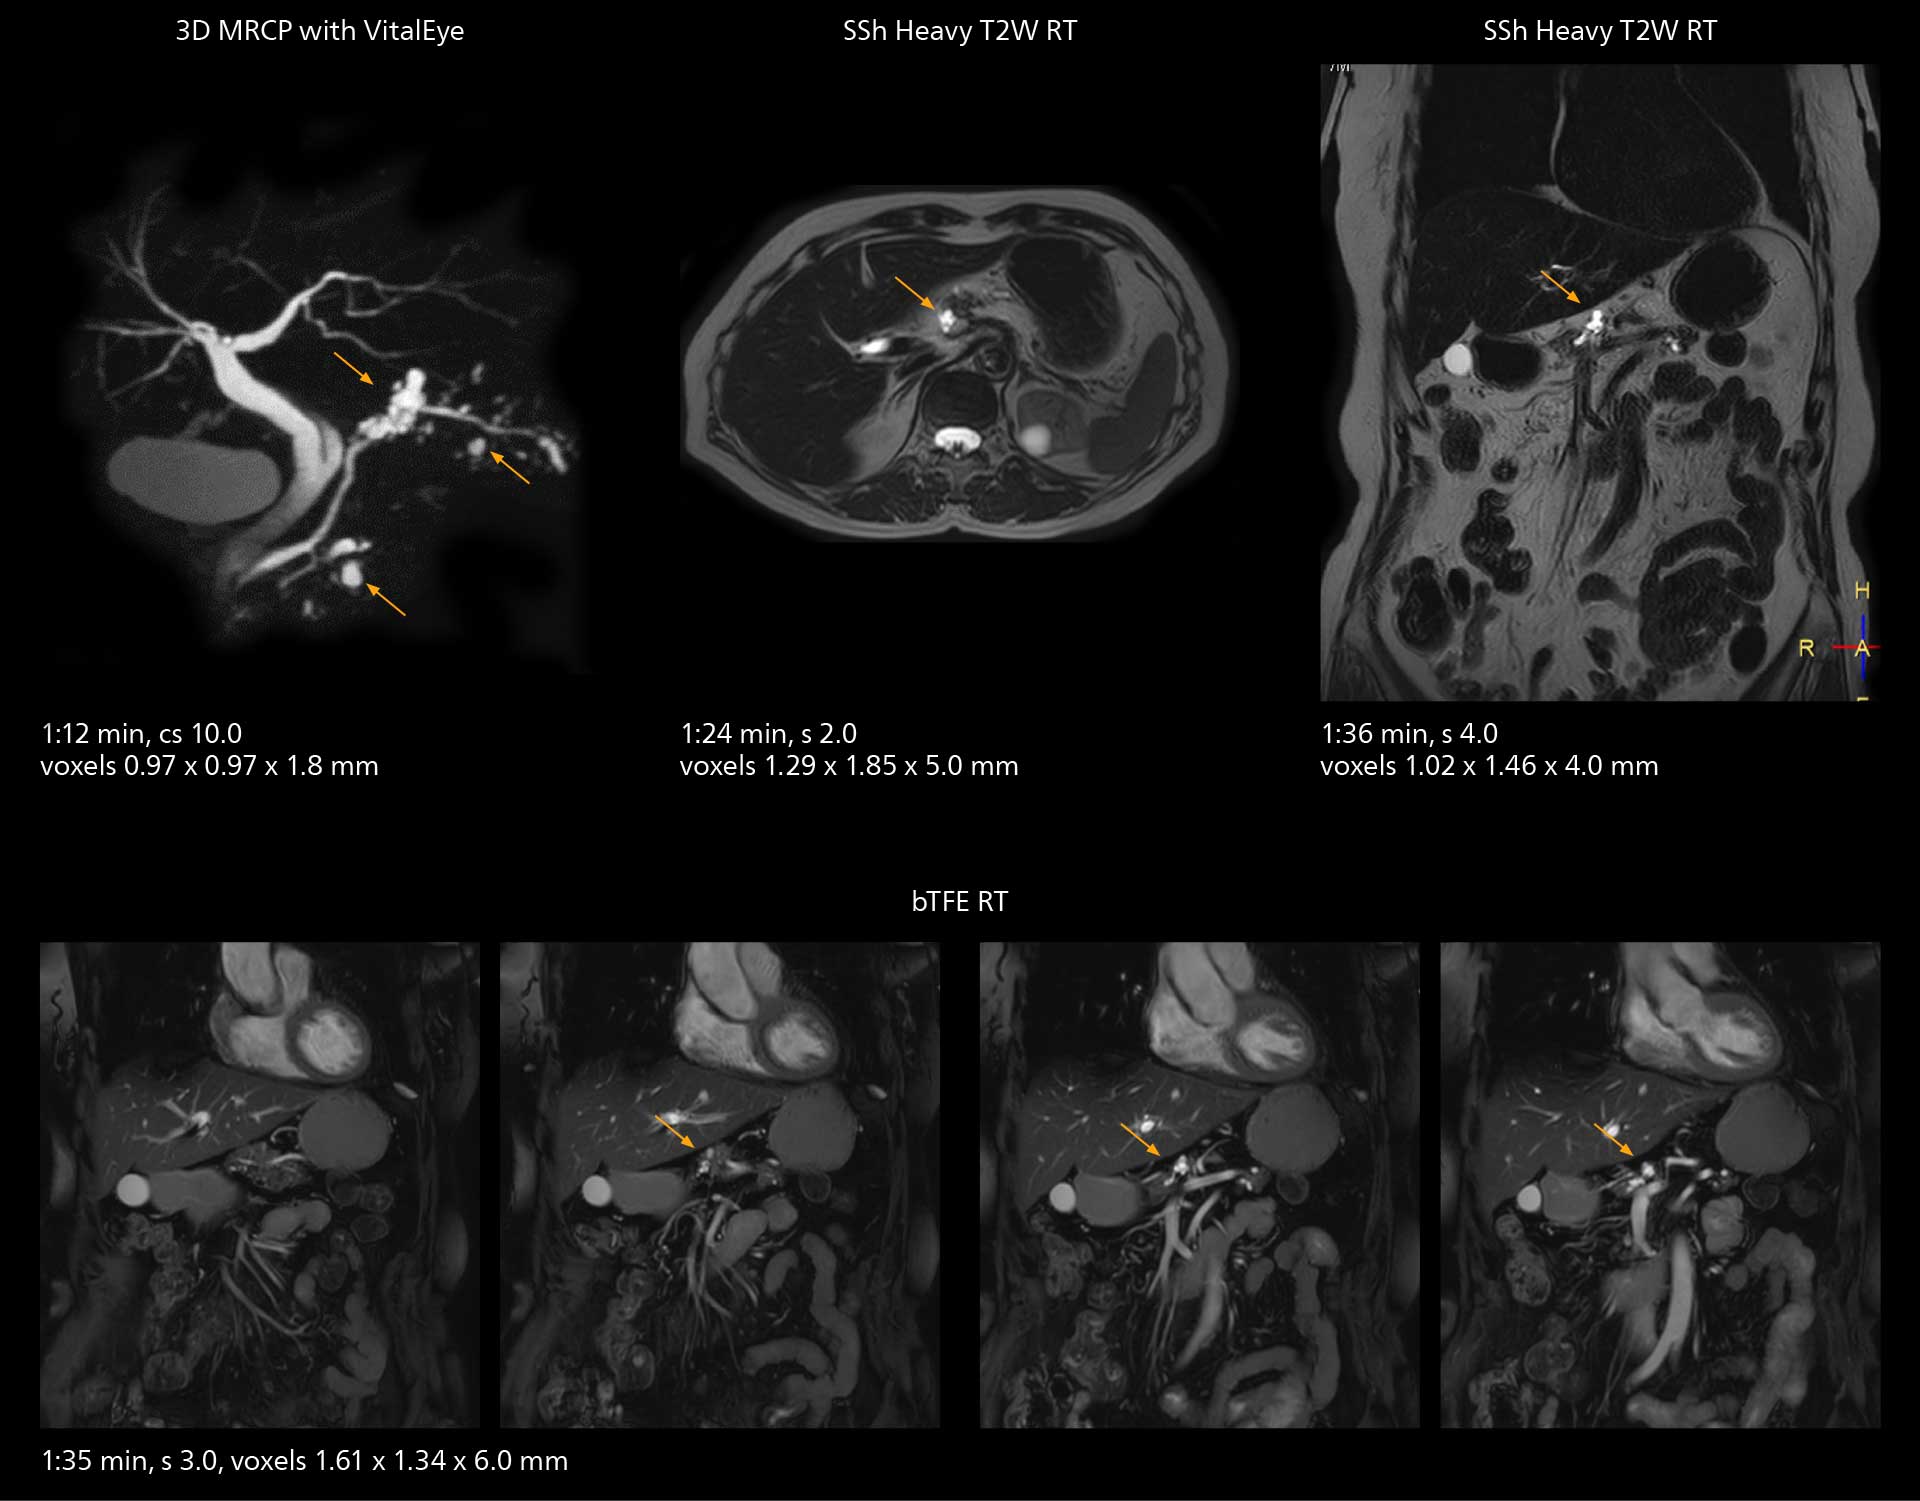

Fast whole body DWIBS examination

With SmartPath to Elition X the team can obtain excellent quality DWIBS imaging and reduce imaging time. Other sequences also fit in the examination slot. This case shows left paravertebral neurogenic tumor and Th10 vertebral hemangiomas.

The value of the Elition X gradients is also evident in DWIBS studies. “The fact that we can consistently obtain distortion‐free DWIBS while reducing imaging time at three coronal stations is excellent,” Dr. Makuuchi says. “In these patients, it’s also important that the application of Compressed SENSE to T2‐weighted, STIR and mDIXON sequences has no impact on the examination time of whole‐body imaging. As a result of the increased speed and higher image quality we realize, DWIBS studies have now become routine examinations.”